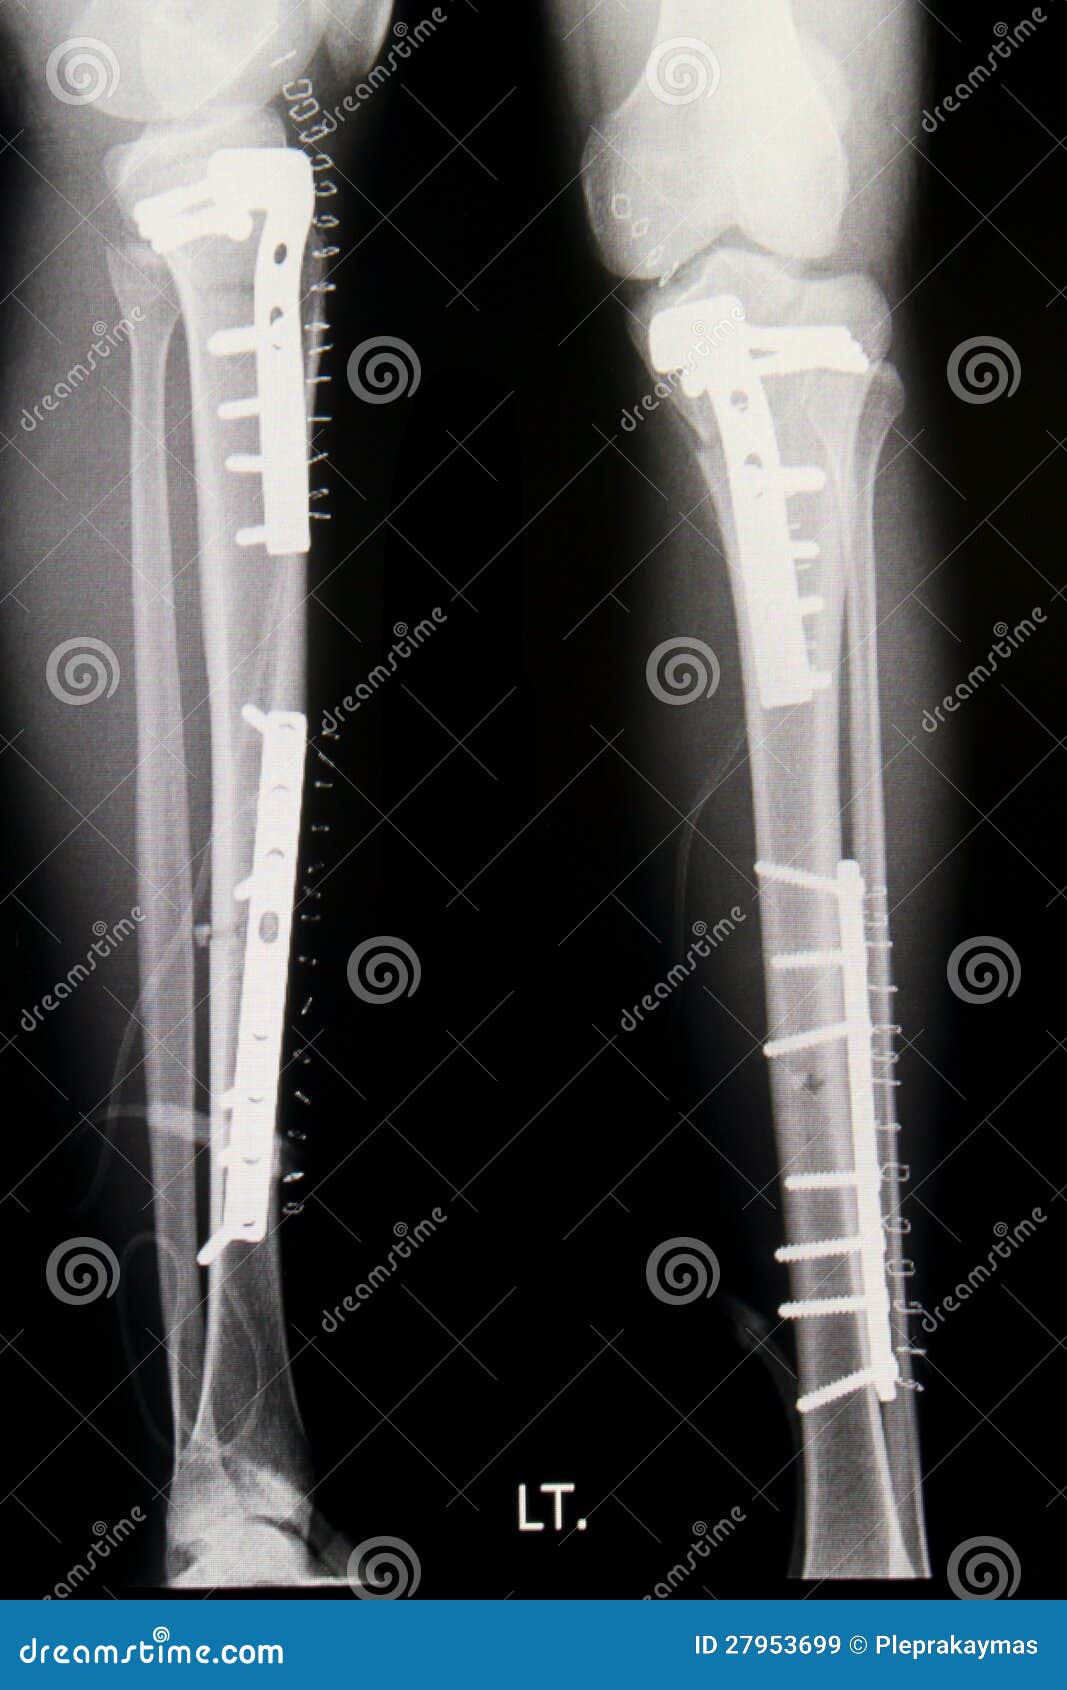

Фото открытого перелома голени

Ниже представлены фотографии открытого перелома голени. Учтите, что изображения могут быть сильно шокирующими и неприятными для просмотра. Если вы не готовы увидеть такие изображения, рекомендуется не продолжать просмотр.